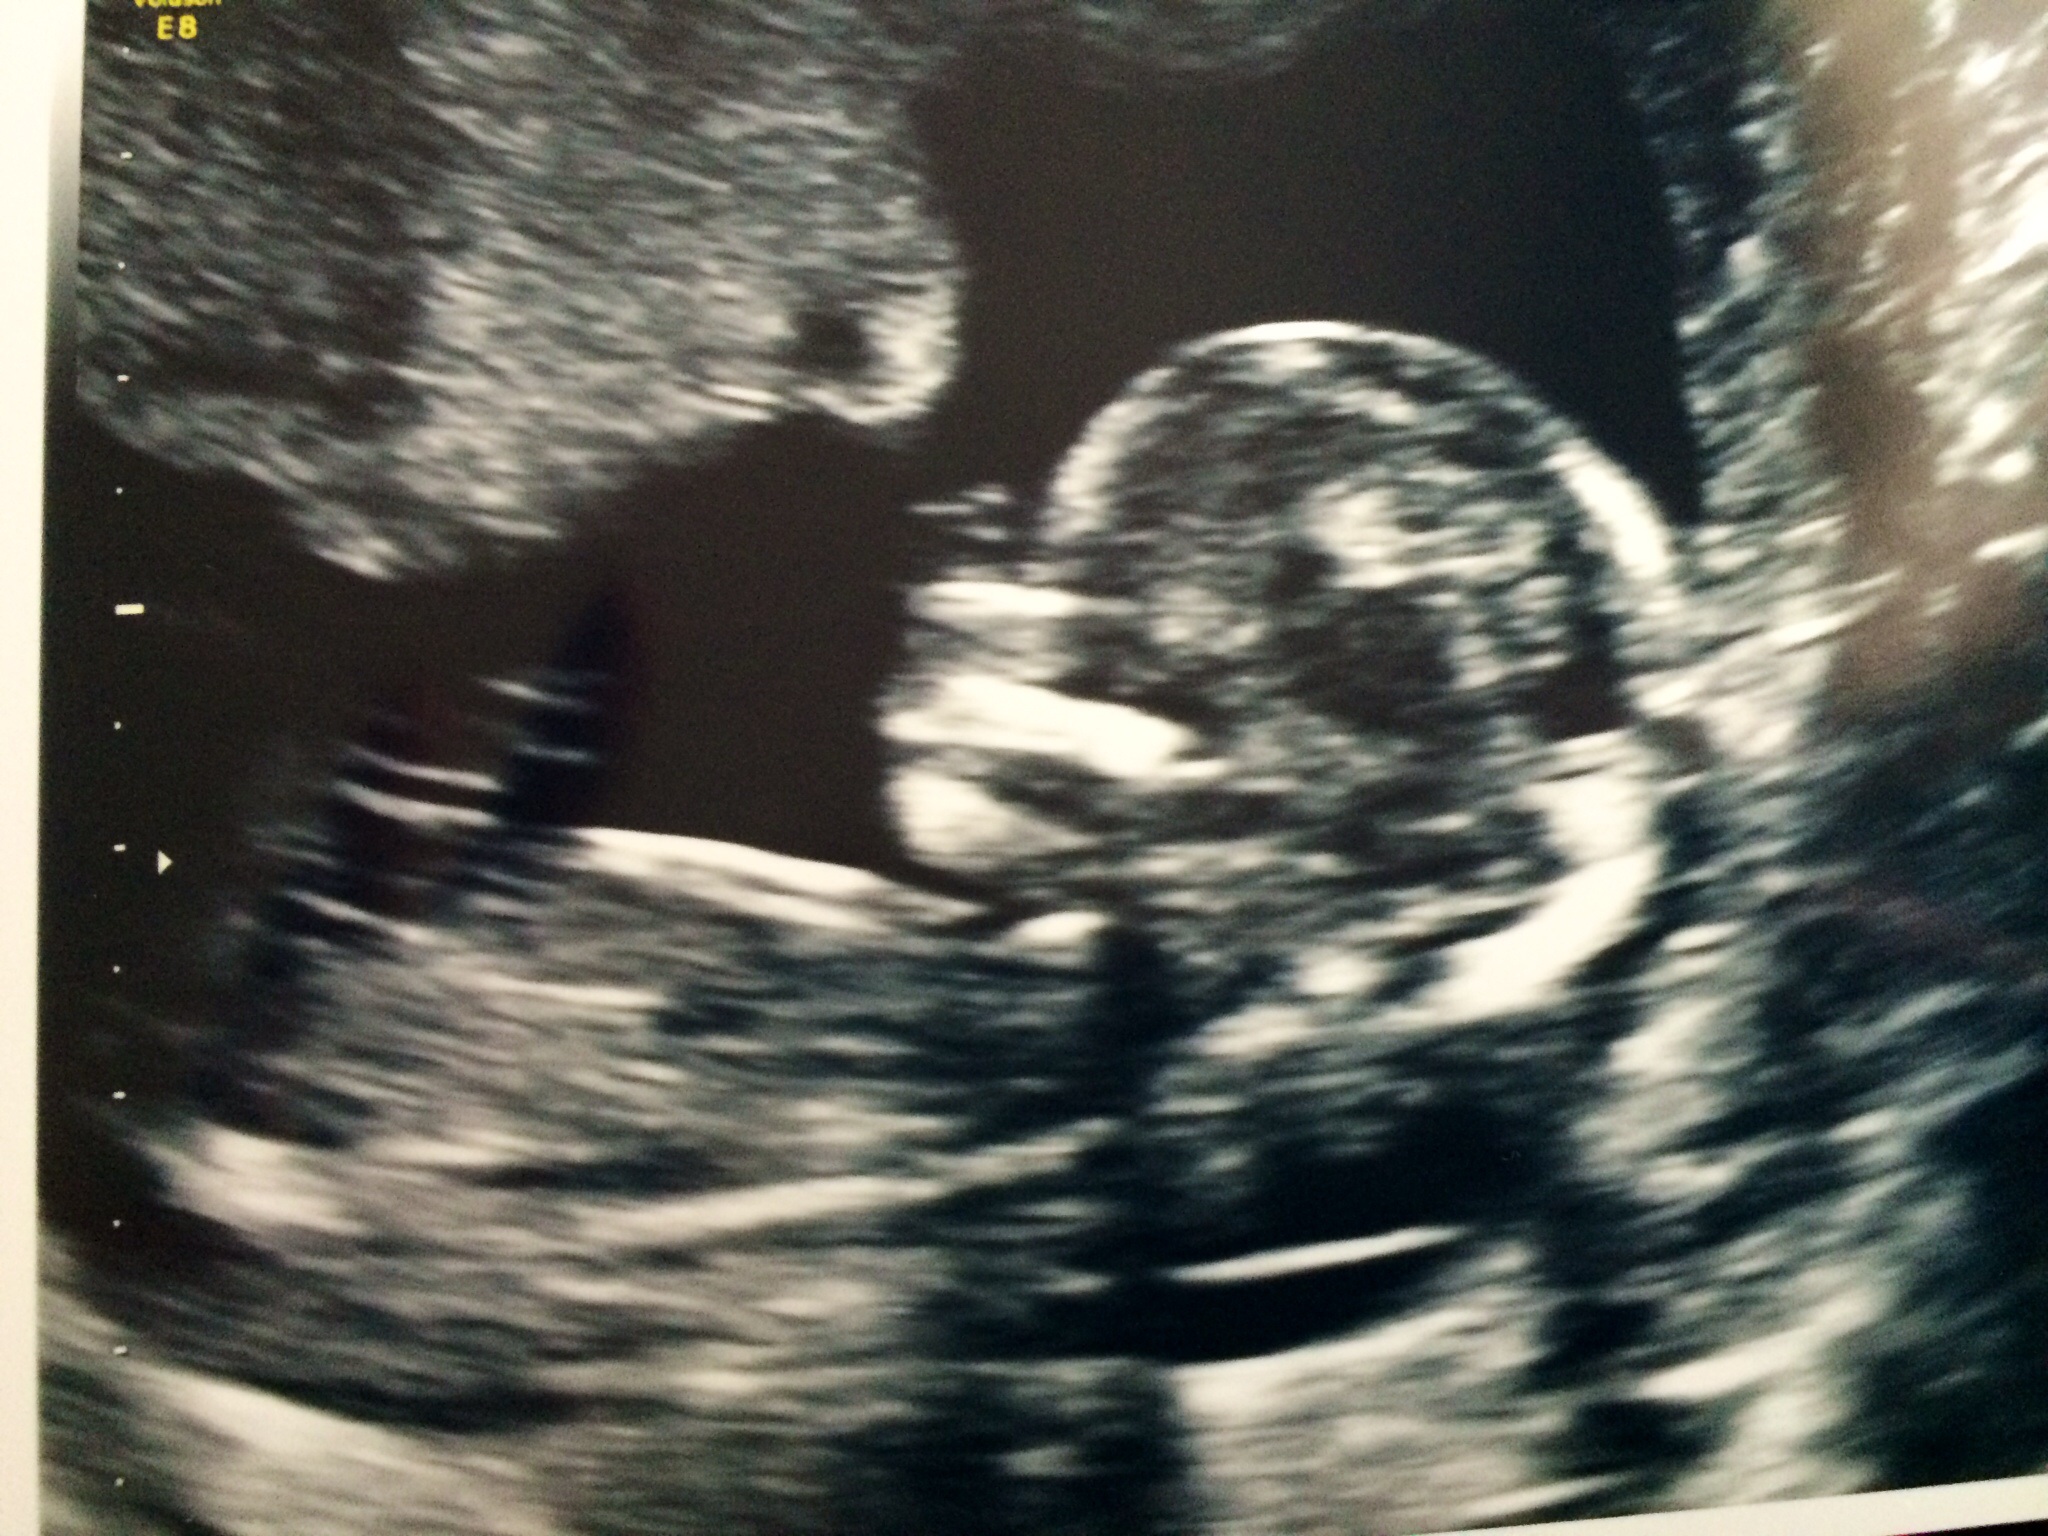

Also I have my NT ultrasound tomorrow. Yay for seeing my baby a 2nd time. My heart is full! :x

I totally understand that! I didn't have my first appointment until 10 weeks and then my first ultrasound at 12 weeks. So much relief after seeing the heartbeat!